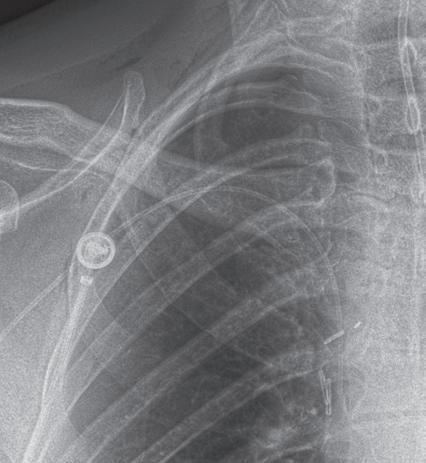

use of digital tomosynthesis in these situations. Additional views of the chest may be required in special instances. Shallow oblique radiographs (15 degrees) may be useful in confirming the presence of a suspected nodule. Forty-five–degree oblique radiographs can be used for the detection of asbestos-related pleural plaques. Apical lordotic views project the clavicles above the chest, improving visualization of the apices and the middle lobe, particularly in cases of middle lobe atelectasis. Lateral decubitus radiographs (Fig. 1.3) can be used to determine the presence or mobility of pleural effusion and to detect small pneumothorax, particularly in patients who are confined to bed and unable to sit or stand erect. A PA radiograph done with nipple markers is useful

In digital tomosynthesis, multiple projections (about 60) of very low-dose x-rays are obtained through the region of interest during a breath-hold of 10 seconds. The acquired data are then reconstructed into contiguous coronal images. At total estimated effective dose of about 0.12 mSv, the radiation dose from digital tomosynthesis is higher than typical PA chest radiographs (0.02 mSv) but significantly lower than most chest CT examinations (2–6 mSv). Compared with plain radiography, digital tomosynthesis provides superior lesion detectability from noise reduction, better depth assessment, and superior contrast resolution. Although the driving application of chest digital tomosynthesis is improved detection of pulmonary nodules over conventional radiography, several other applications have been assessed as well—for example, suspected interstitial lung disease, cystic fibrosis, airway evaluation, and evaluation of thoracic skeleton fractures. Studies have shown that digital tomosynthesis can help detect more pulmonary nodules smaller than 9 mm in diameter compared with combined PA and lateral chest radiographs (Fig. 1.8).